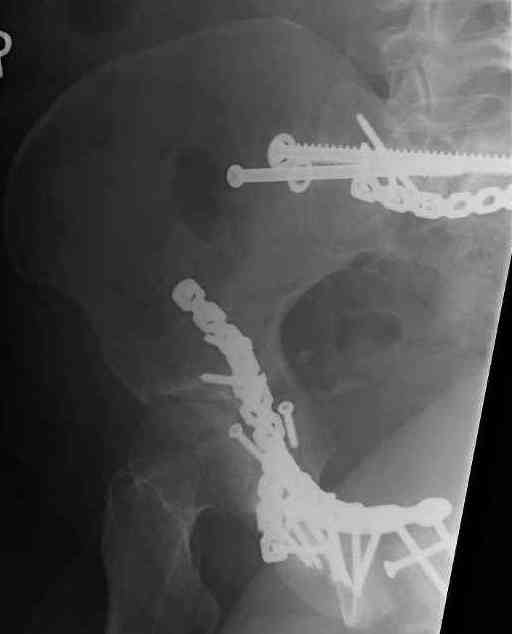

Looking for advice. This is a 48 yo non-smoking female s/p MCC 10 months ago. I do not have the initial injury films. She underwent ORIF as shown on attached file. She is having continued pain in low back/sacral region. Worse with sitting and prolonged walking. Has had pain since surgery. All of her wounds have healed uneventfully. Also has right hip pain laterally. No groin pain. Not aggravated with ROM of the hip. Infection work-up has been negative.

Any thoughts on the broken plate on the pelvic brim and the non-union on the anterior column. Doesn't seem like she's have pain from there.

Suggestions on treatment of sacral nonunion.

Thank you...it might help to remove the disengaged and other iliosacral screws then insert longer lag screws into the upper sacral segment and if anatomically feasible into the second sacral segment as well.

You could do it percutaneously and even add an electrical stimulation device if that seems reasonable.

At this point, I'd ignore the right pubic root issue if asymptomatic.